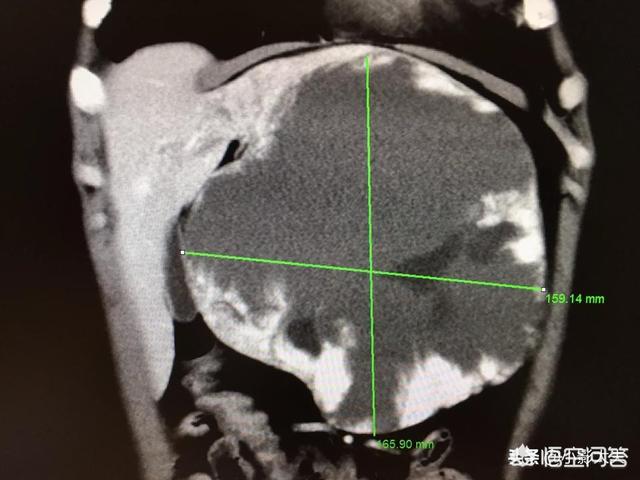

上の画像は肝血管腫のCT画像で、右葉に低密度の陰影があり、境界が明瞭で、増強後に端から中心に向かって漸増する。

下は私が今まで見た中で最大の肝血管腫で、16cmの大きさ、54歳の女性、心窩部痛のために受診した。

大きな血管腫とは、大きさが5cmを超えるもので、肝臓領域の痛み、肝機能異常、肝臓の端に位置する血管腫など、著しい圧迫を伴う症状を呈するものである。上記のような症状があり、大きさが16cmの女性患者は積極的な治療が必要である。